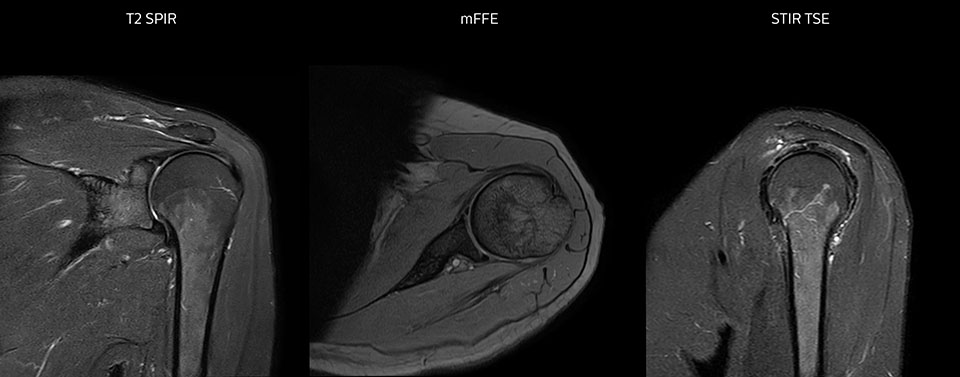

Die Prodiva Schulterspule ist sehr flexibel und hat eine große Abdeckung; dies erleichtert eine gute Positionierung, was wiederum zur ausgezeichneten Bildqualität und hohem SNR beiträgt, die wir in unseren Schulteruntersuchungen erreichen.

Scandauer: 2:55 Minuten, FOV: 160 mm, erfasste Voxel: 0,55 x 0,83 x 3,0 mm.

Scandauer: 04:19 Minuten, FOV: 160 mm, erfasste Voxel: 0,55 x 0,80 x 3,0 mm.

Scandauer: 02:50 Minuten, FOV: 160 mm, erfasste Voxel: 0,70 x 0,99 x 3,0 mm.